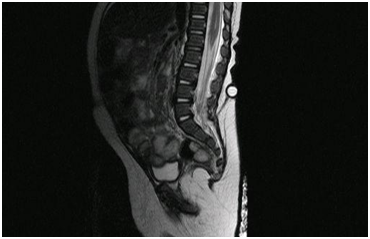

A 5-month-old infant that arrives to the pediatric emergency room (ER) with a chief complaint of fever of 12 hours (38ºC axillary), associated to vomits and irritability. A perinatological history of a pilonidal sinus within the center of a lumbosacral angioma detected at birth stands out, with an initial medullar ultra sonography that did not detect any communication. The rest of variables were within normal range. The physical exam revealed an angiomatous cutaneous lesion in the lumbosacral region L5-S1 with a pilonidal sinus and a hair follicle in the center of the lesion (Figure 1). Blood work showed WBC: 21300/mm3 (PMN 59%, Bands 3%, Lymphocytes 29%, Monocytes 9%), CRP: 143, 2mg/L and Procalcitonine: 2, 39ng/mL; VGB and the rest within the normal range. The CSF obtained was of purulent aspect, CSF cell count: WBC 8240/mm3 (PMN: 82%), CSF glucose: 0.18mg/dL, CSF protein: 0.86g/L, CSF gram stain: Gram negative bacillus, CSF culture grows an E. coli. Immunologic study without alterations. The patient was admitted and started treatment with cefotaxime (300 mg/kg/day),3 showing a clinical improvement within 6 hours of starting the treatment. The antibiotic was maintained for 22 days, with normalization of the CSF values by the end of the treatment.5 A new medullar ultrasound in the lumbosacral region was performed finding a hypoechoic tubular image starting form a hyperechoic subcutaneous nodular lesion in the sacral region that continues in depth into the sacral osseous elements. An MRI was then performed observing a fistula starting in the lumbosacral pilonidal sinus and continuing into the dura mater with a sacral osseous dysrafia (Figure 2). Within a month of discharge, and while waiting for the corrective neurosurgery, the patient presents with a new meningitis by E. coli, starting treatment again with cefotaxime (300mg/kg/day), receiving antibiotic treatment for 30 days in this second episode. A few days before ending the second course of antibiotics the surgical correction was successfully performed, with a resection of the cutaneomeningeal fistula and closure of the plains from skin to sacral meninges. Following the surgery, the infant has remained asymptomatic and has not presented any complications or new infections.